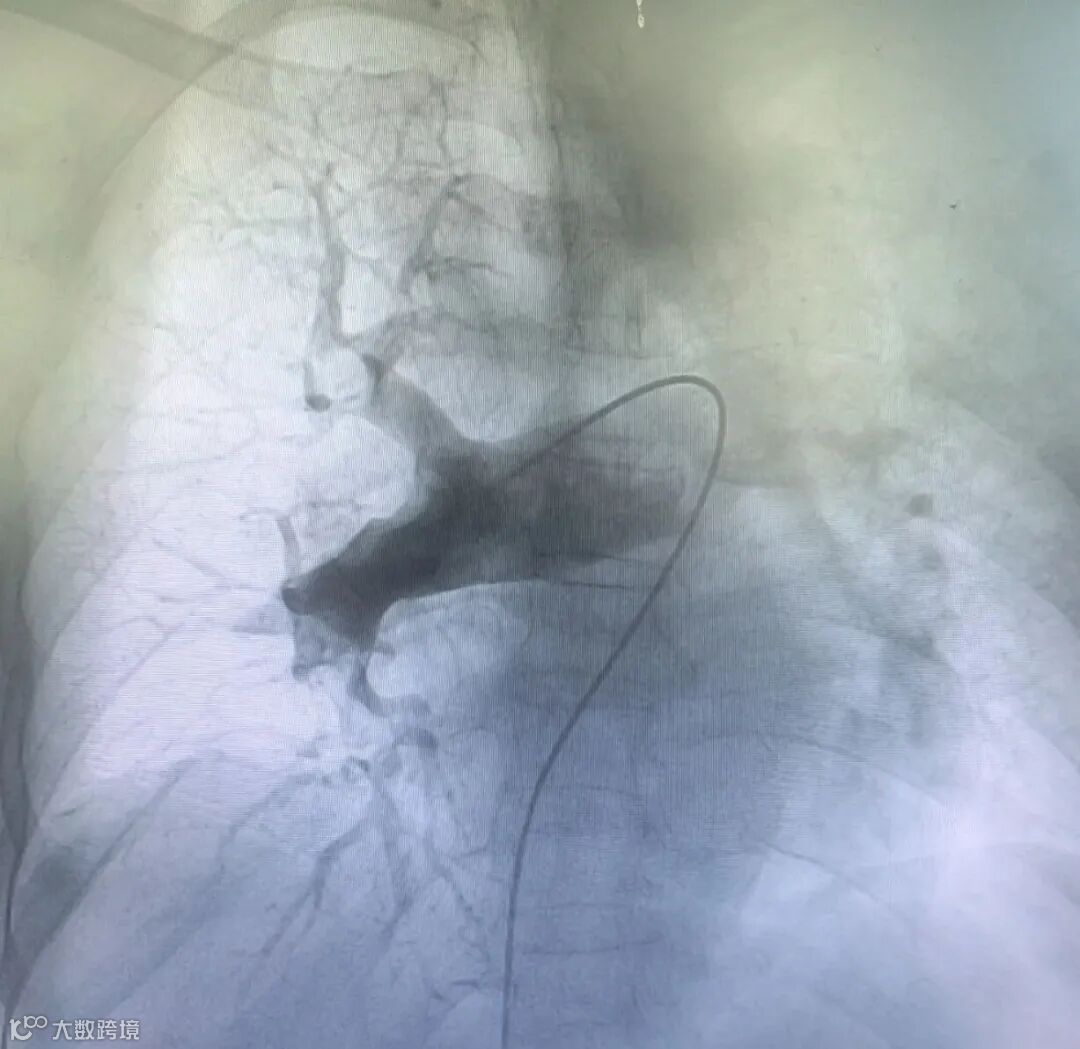

更换置换 22F 血管鞘 , 送入Tendvia®抽栓导管置于右肺动脉血栓近端行血栓抽吸治疗 , 抽取大量红色血栓。将Tendvia®肺动脉取栓支架沿导丝通过抽吸导管向前推送⾄右肺动脉血栓位置,支架头端穿过血栓 ,回撤输送鞘管 ,支架自动膨开 ,等待 90 秒 ,连接抽吸器并形成负压 ,回撤取栓支架的同时旋转开关释放负压,血栓由支架收集后进入抽吸导管内 ,并在负压抽吸状态下进入抽吸导管中。右肺动脉血栓清除后 ,同样方法清除左侧肺动脉血栓。

取栓中